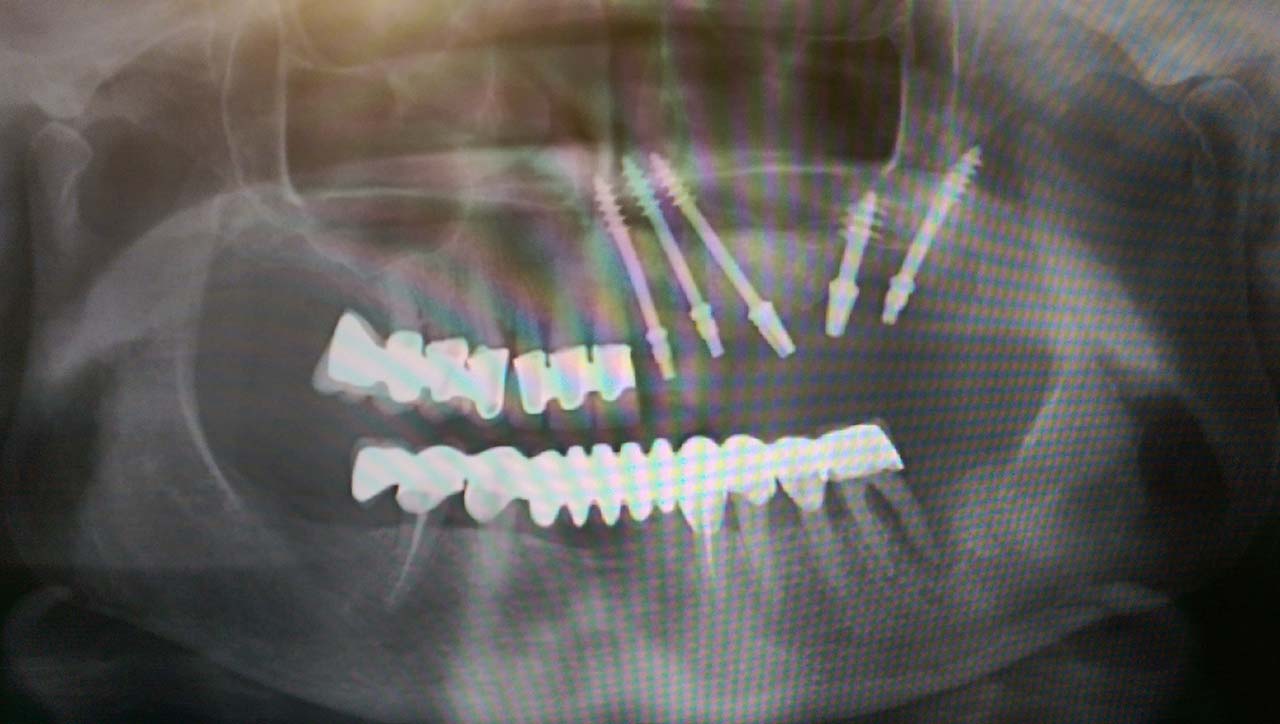

Teljes szájüregi rehabilitáció két lépésben

Ismét egy teljes szájüregi rehabilitáció két lépésben. Először az alsó fogak lettek kihúzva és azonnal implantálva, híddal ellátva, majd később a felső. IHDE svájci azonnal terhelhető implantátumok és cirkónium hidak. Dr. Kelemen Péter és a Symbion Fogtechnika közös munkája.